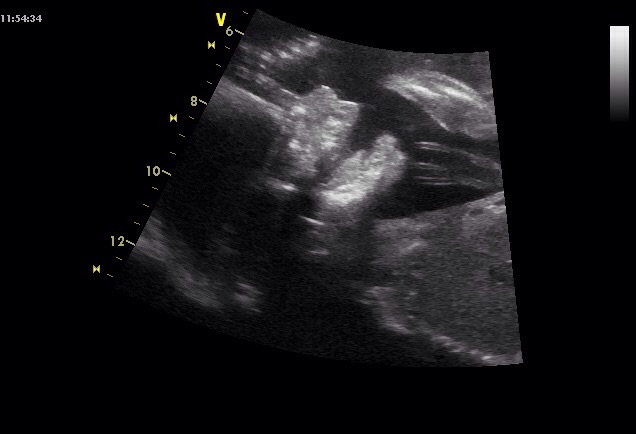

Hezké ráno -) včera jsme byli na screeningu a čekáme chlapečka .jsem 20+4 a prcek je prý podle tabulek 348g a krásně fotky jsme dostali .Prikladam